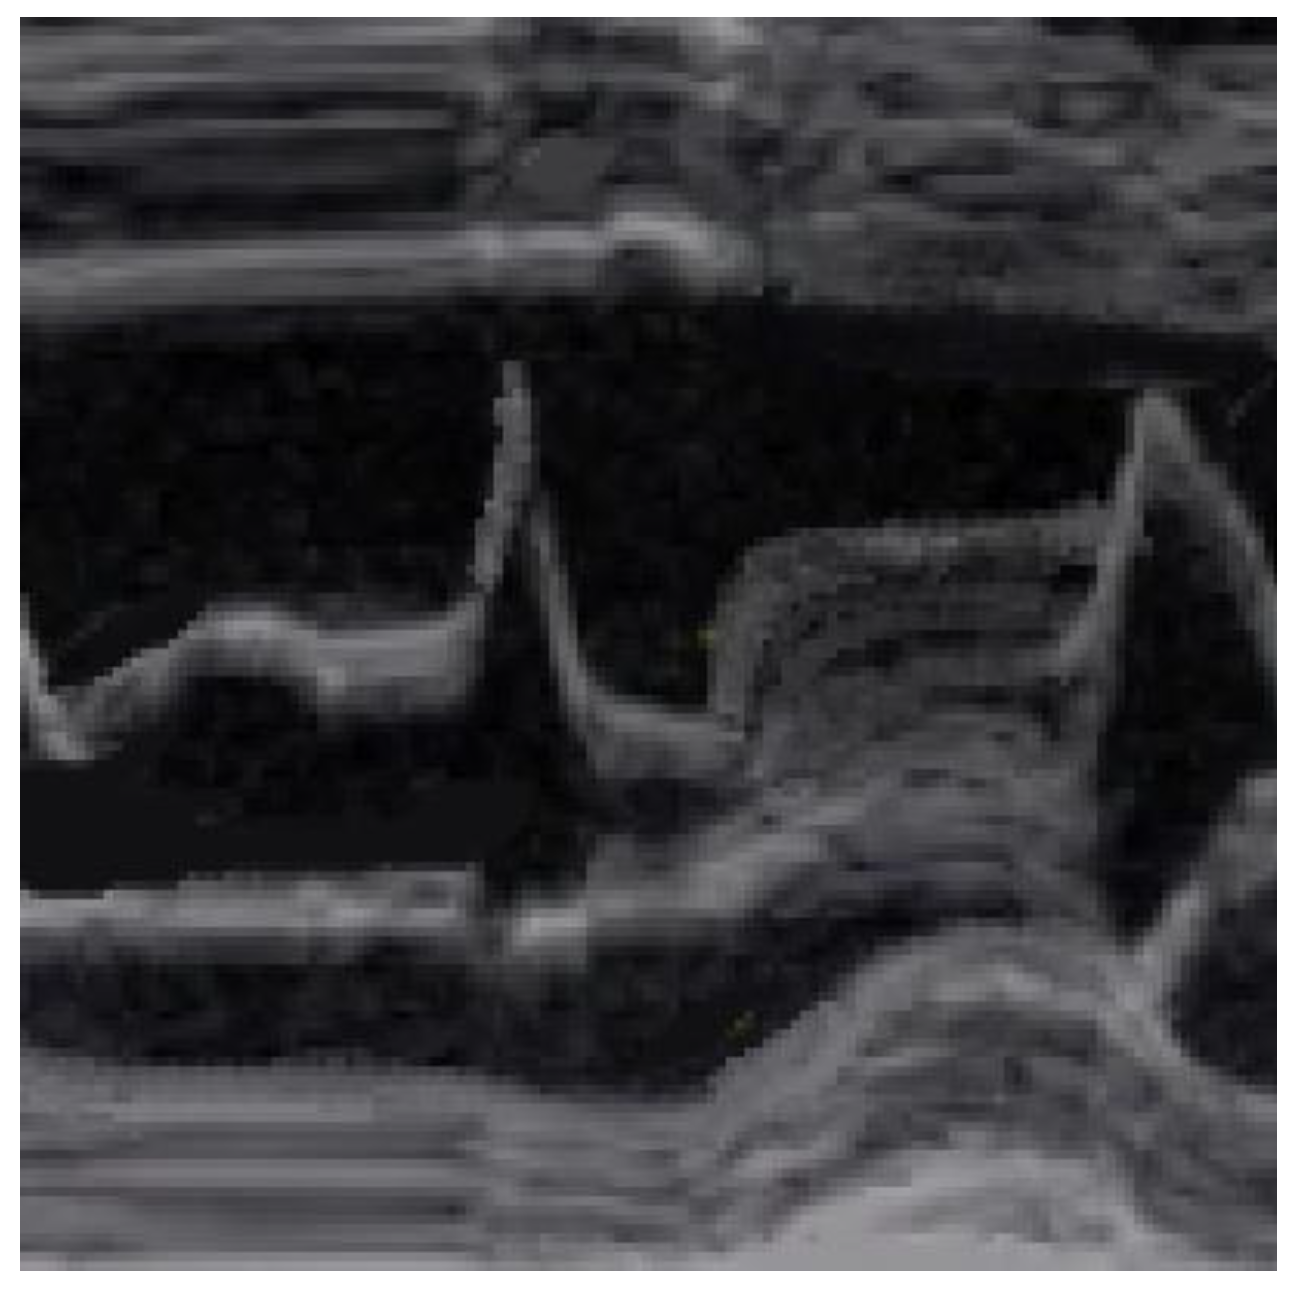

SAM and its severity are assessed via the M-mode from a short-axis view at the mitral valve level. SAM is defined as (1) incomplete if the mitral anterior and/or posterior leaflets do not touch the IVS, as (2) mild if mitral–septal contact occurs in the late systole and for less than 10% of the duration of the systole, and as (3) severe if it starts mid-systole and occupies more than 30% of its duration.

SAM is characterized by an abrupt anterior movement of the mitral valve during contraction, reaching its peak before the maximum movement of the posterior wall; this characteristic allows the differentiation of true SAM from SAM produced by an exaggerated anterior motion of the mitral valve, which reaches its peak after the full contraction of the posterior wall, i.e., “pseudo-SAM” [14] (Figure 3).

Figure 3.

Pseudo SAM: the peak of SAM reaches after the full contraction of the posterior wall.